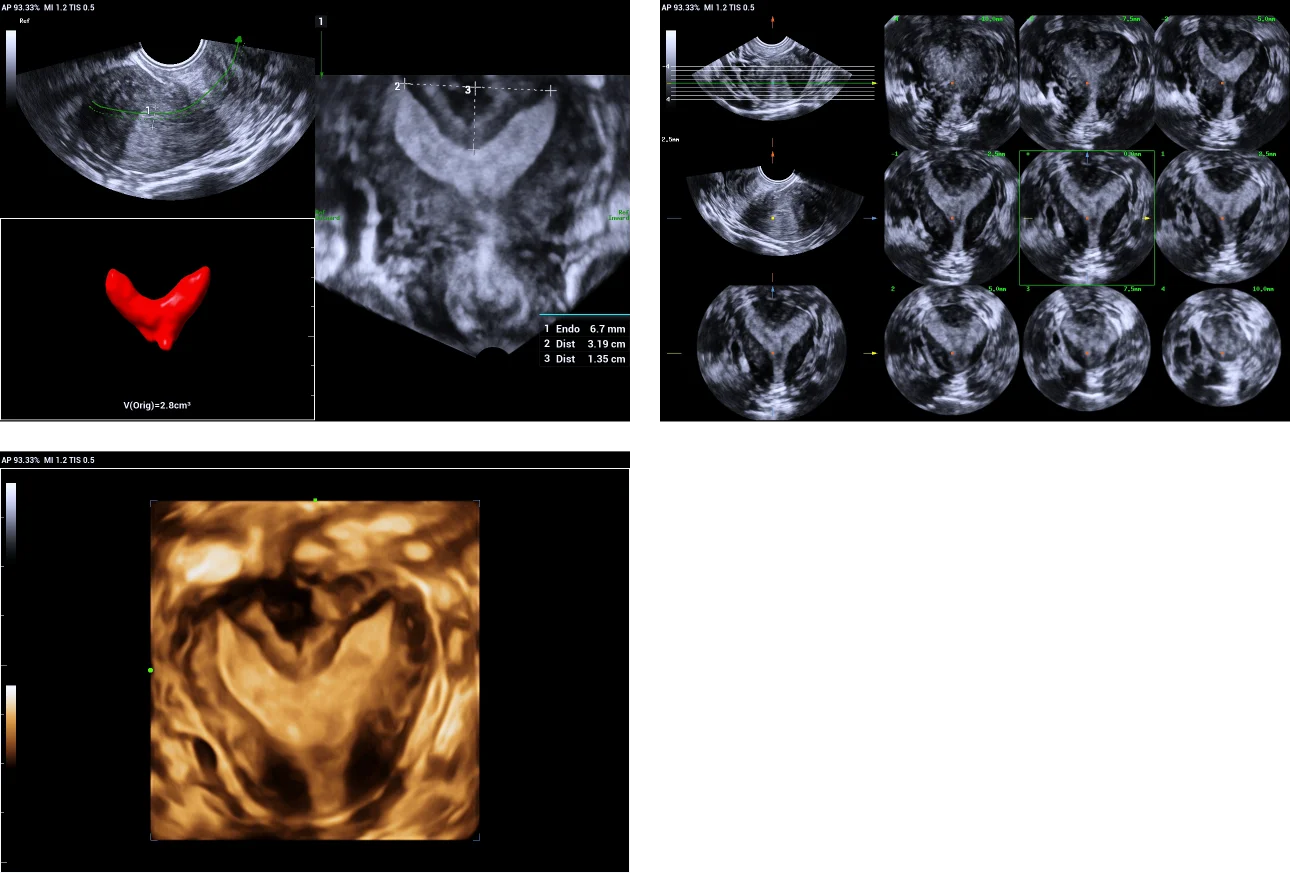

3. Uni-cornuate uterus.

Use of Smart ERA in diagnosis of Mullerian duct abnormalities - Uni-cornuate uterus

Unicornis-unicolis with no rudimentary horn, type b according to American Fertility Society classification.